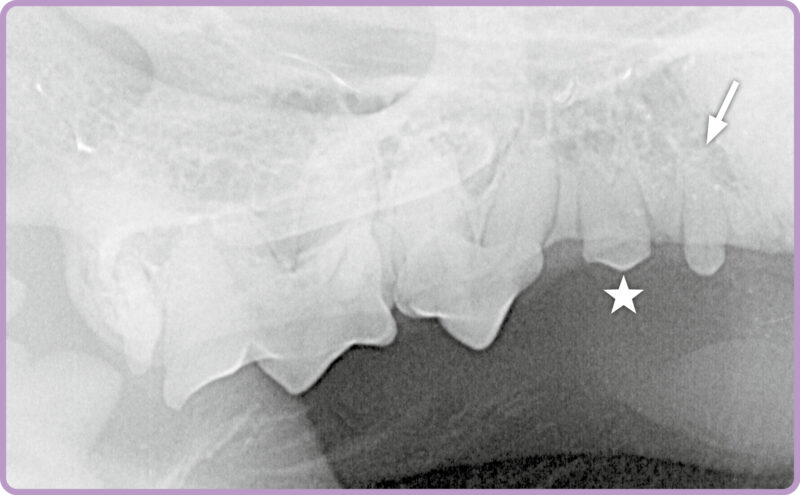

Röntgenbeispiel Katze: Die Aufnahme einer Katze (Abb. 1) zeigt eine überzählige Wurzel des zweiten Prämolaren (⭐️) im Oberkiefer rechts. Darüber hinaus wird auch ein zusätzlich angelegter Zahn im Bereich des zweiten Prämolaren

sichtbar (➡️).